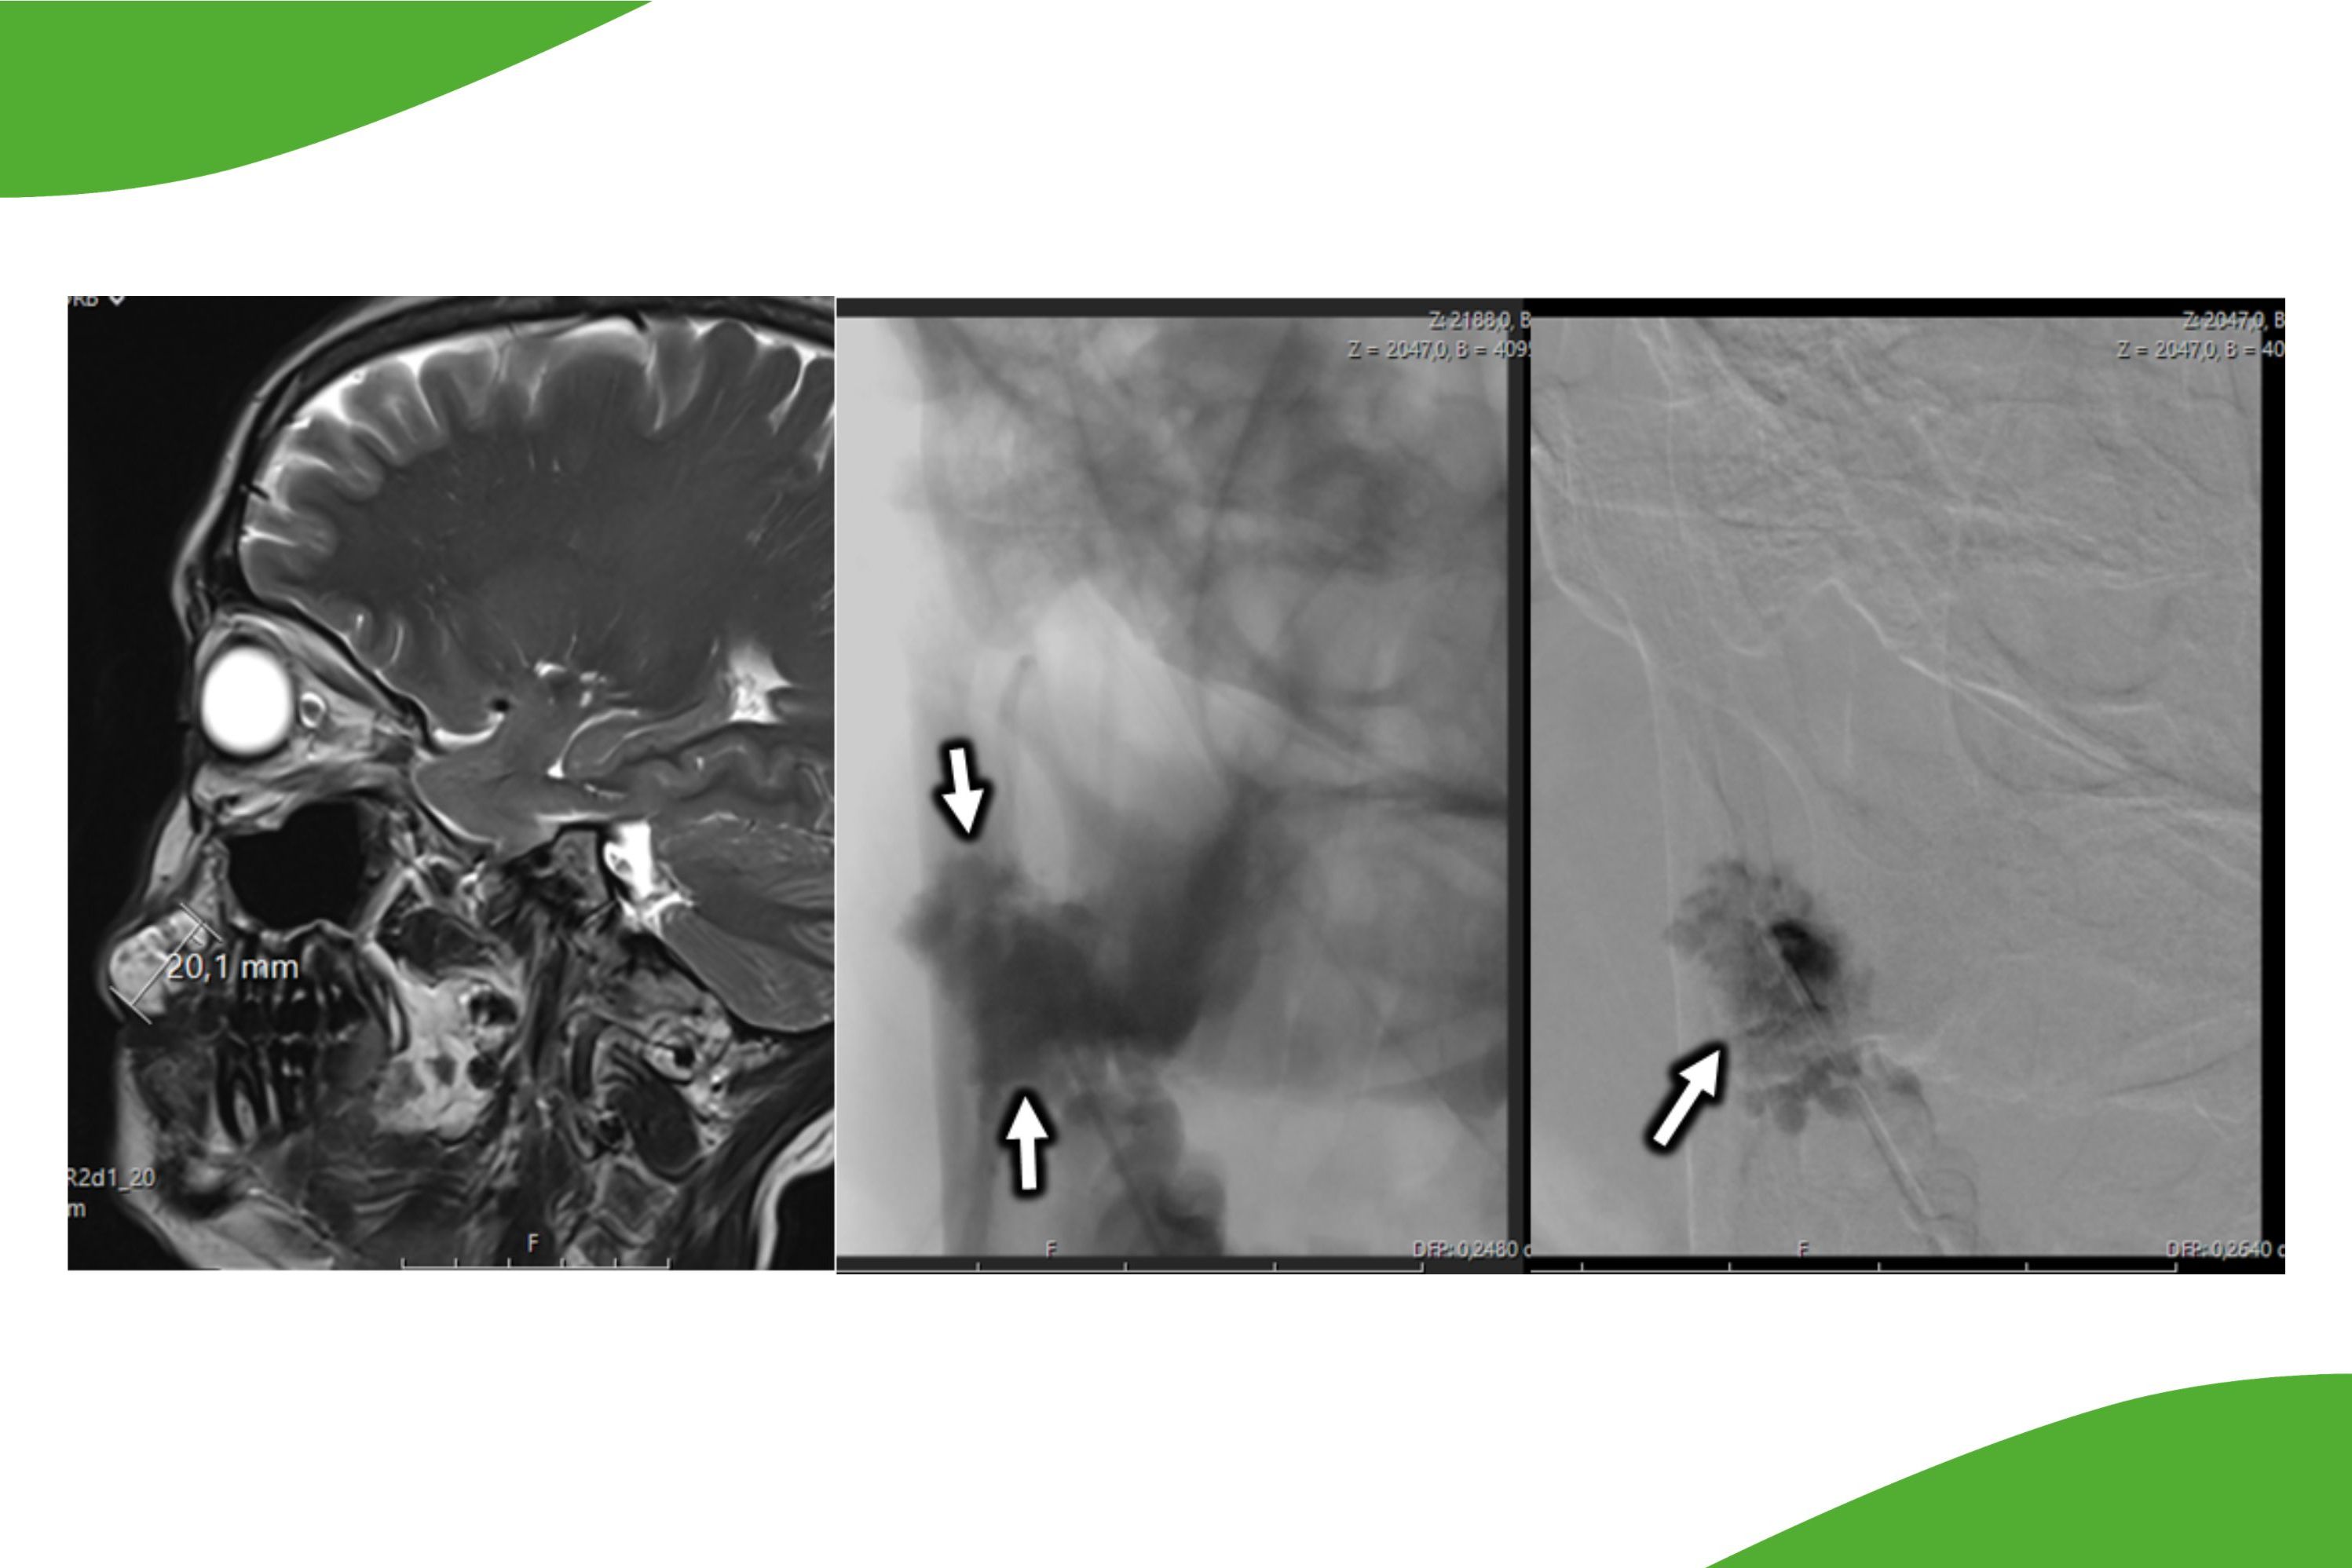

Bei Gehirnblutungen:

Eine Gehirnblutung kann unterschiedliche Ursachen haben, zum Beispiel ein Aneurysma oder Gefäßmissbildungen. Um zu differenzieren, aus welchem Grund eine Hirnblutung aufgetreten ist, wird eine Angiographie der vier gehirnversorgenden Gefäße durchgeführt.

Anhand dieser Untersuchung kann dann eine gezielte Behandlung geplant werden. Hier kommen neben der operativen Therapie durch die Neurochirurgie auch die interventionellen neuroradiologischen Verfahren mit sog. Coiling und Embolisieren in Betracht (siehe spezielle Behandlungsmethoden im Kopf-Halsbereich)

Großes Hirnaneurysma im Bereich der Arteria basilaris (sogenanntes Basilariskopf-Aneurysma), welches durch die raumfordernde Wirkung symptomatisch geworden ist.

Beispiel einer Angiographie der Gesichtsarterie mit Darstellung einer komplexen Kurzschlussverbindung zwischen Arterien und Hirnvenen (sog. durale AF-Fistel).